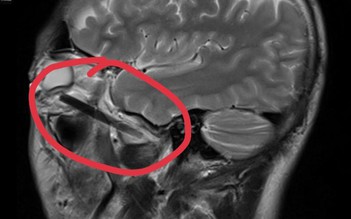

Nếu không được các bác sĩ phẫu thuật kịp thời và thành công, người đàn ông 42 tuổi suýt nữa đã mù mắt vĩnh viễn do bị u nhầy hốc mắt vì biến chứng sau vài lần mổ viêm xoang.

Mắt mờ không đọc báo được, người đàn ông suýt mù vì khối u nhầy hốc mắt